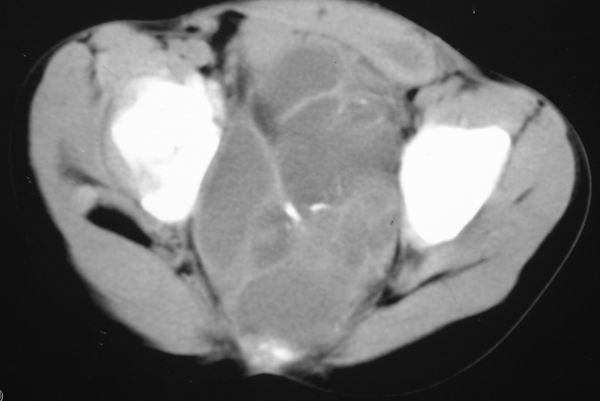

标题: PED0321:F 7 骶尾部肿瘤 有病理结果 [打印本页]

标题: PED0321:F 7 骶尾部肿瘤 有病理结果

骶尾部肿瘤 有病理结果

畸胎瘤

考虑畸胎瘤可能性大。骶尾骨无破坏。不考虑脊索瘤。

骶骨没有发现骨质破坏,畸胎瘤的可能性大